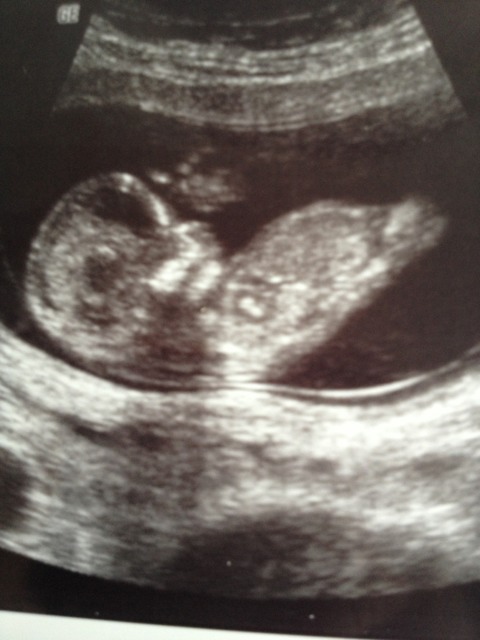

I dont see a nub in the two first and in the third i think its the leg, not a nub. But im no expert:)

First picture looks like an obvious boy nub. I don't see a nub in the other photos ...